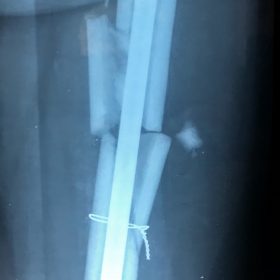

Κατάγματα Μηριαίου ή Κνήμης

Τα κατάγματα της Διάφυσης των οστών της κνήμης και του Μηριαίου οστού στη σύγχρονη ΟΡΘΡΟΠΑΙΔΙΚΗ αντιμετωπίζονται με ΕΝΔΟΜΥΕΛΙΚΗ ΗΛΩΣΗ.

Δύο τομές 3 εκατοστών και 1 εκατοστού αντιστοίχως για την εισαγωγή και το κλείδωμα του ήλου μέσα στο οστό. Η μέθοδος είναι κλειστή,σχεδόν αναίμακτη,διάρκειας 60 λεπτών,με τη βοήθεια C-ARM (τηλεόρασης).

Στον ασθενή παρέχεται οπτικό υλικό (όλα τα χειρουργικά στάδια) σε CD ή Στικάκι,λόγω της δυνατότητας καταγραφής του χειρουργείου από το C-ARM Ο ασθενής περπατάει άμεσα μετεγχειρητικά στις 5 ώρες μετά την επέμβαση και εξέρχεται από το νοσοκομείο σε 1 -2 ημέρες.